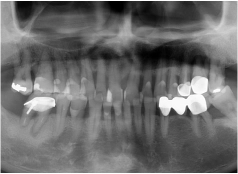

• Tình trạng răng trước đây:Mất nhiều răng, bị tiêu xương hàm

• Cấy ghép 6 trụ Implant loại Implant Mis C1 Đức

Kết quả nhận được cũng đúng như mong muốn của chú. Trụ Implant tích hợp thành công vào xương hàm, sau 4 tháng đã có thể gắn răng sứ cố định và chú ăn uống thoải mái ngay sau đó. Từ ngày có hàm răng mới chắc khỏe, chú Hùng không còn phải chịu nỗi cám cảnh đau nhức mỗi khi ăn uống, nhờ đó tâm lý cũng thoải mái hơn rất nhiều.